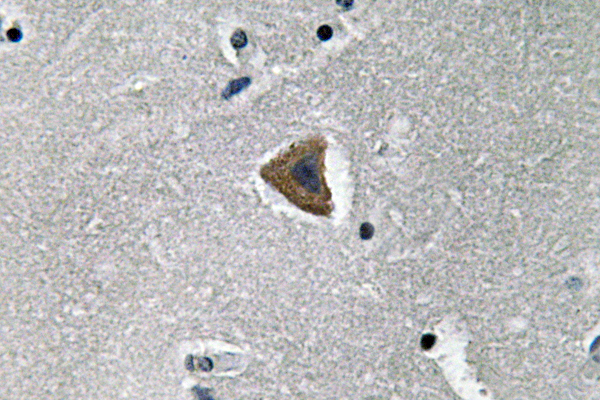

IF-P,IF-F,ICC/IF,WB,IHC-P,ELISA

稀释比(Dilution Ratio)

IF-P/IF-F/ICC/IF 1:50-200, WB 1:500-1:2000, IHC-P 1:100-1:300, Immunocytochemistry 1:200-1:1000, ELISA 1:20000.Not yet tested in other applications.